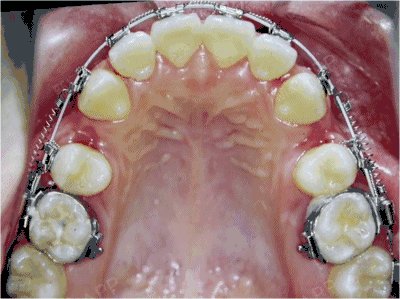

临床病例应用靴形曲拉尖牙向后时增强后牙支抗(上牙合面像)

图片尺寸768x512